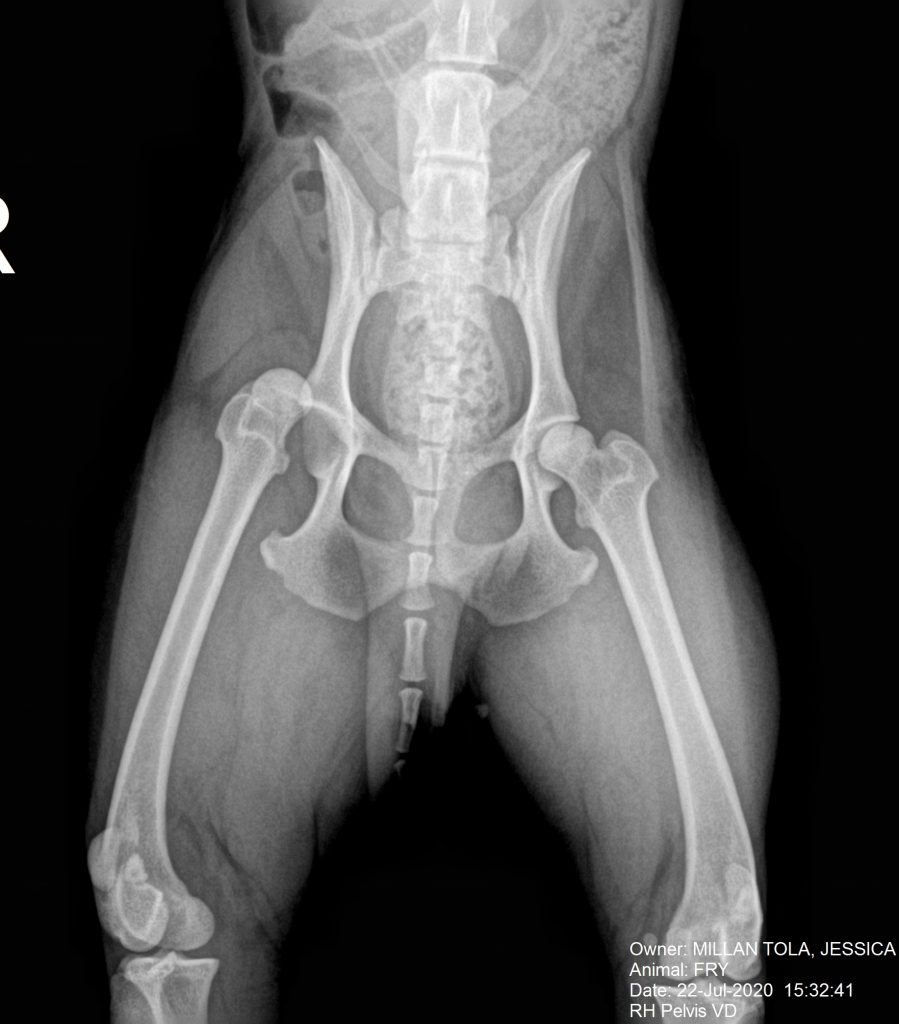

Fry es un macho de cuatro años de edad, que sufrió un accidente de tráfico. Fue atendido en un centro de urgencias y tras la estabilización solo detectaron una luxación de la cadera derecha.

En la radiografía V-D de la pelvis se aprecia la luxación de la articulación coxofemoral del lado derecho.